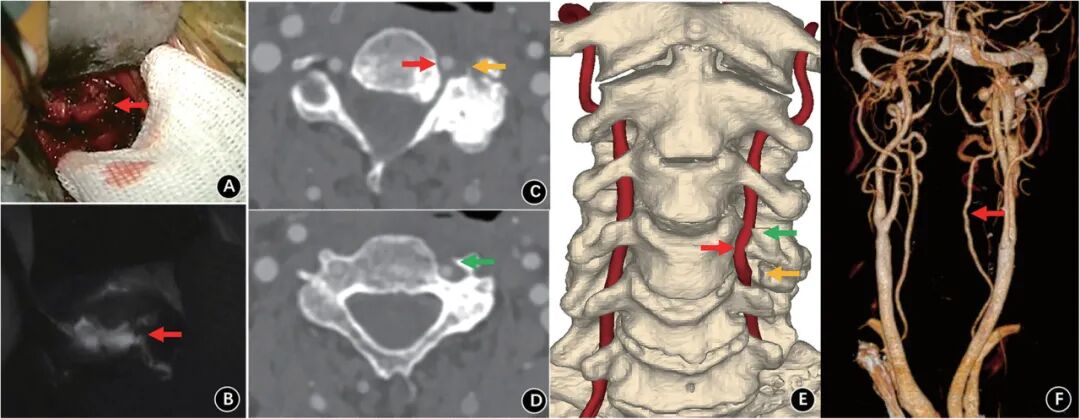

病例报道:77岁男性,出现眩晕、步态不稳和吞咽困难,CTA和DSA显示颈4/5小关节增生压迫椎动脉并95%闭塞。前路椎动脉减压后,椎基底动脉供血不足症状消失。

第二,这例是椎动脉型颈椎病吗?我认为不是。因为,颈椎病的定义是退变性疾病,本文的骨质增生我认为是病理性增生,不应算做退变性增生。增生的原因我估计是小关节慢性低毒性感染,增生的部位是小关节和钩椎关节,横突孔不确切。我对椎动脉型颈椎病的观点在以前的文章中表达过:椎动脉型颈椎病到底存在吗?我国教科书对本病的定义是:因各种机械性与动力性因素(退变性)致使椎动脉遭受刺激或压迫,以致血管狭窄、折曲而造成以椎基底动脉供血不全,引起偏头痛、耳鸣、听力减退及耳聋、眩晕、视力减退、视物模糊、复视等症状。我个人的观点,不认同椎动脉型颈椎病的存在,理由如下:1.教科书描述的横突椎动脉孔骨质增生狭窄压迫椎动脉在理论上不成立。骨质增生本质是关节不稳和异常活动引起慢性损伤,继而骨膜下出血,骨膜细胞、间充质细胞等在细胞因子的作用下向骨细胞分化过程。椎动脉孔没有形成关节,故不会骨质增生和增生性狭窄。2.钩椎关节退变性骨质增生压迫椎动脉,我没有见到文献证据很好的图片。椎动脉毕竟与钩椎关节有一定的距离,而且有较好的弹性,只存在理论上的被压迫。3.旋转椎动脉闭塞综合征(也称为Bow-Hunter’s综合征、Powers’s综合征)是一种少见疾病,因为已有神经内科单独命名,不应归结于椎动脉型颈椎病。4.即使偏头痛、耳鸣、听力减退及耳聋、眩晕、视力减退、视物模糊、复视等症状由椎基底动脉缺血引起,目前文献与颈椎退变有关循证证据并不强,应由神经内科诊断和处理。5.即使有人没有很强证据地猜测交感神经兴奋引起椎动脉痉挛,这怎么说也该由神经内科诊断和处理。第三,时代的进步。1994年新疆医大欧阳甲教授在Spine杂志首次报道椎动脉显露减压治疗15例混合性颈椎病,文后出现大名鼎鼎Magerl的Comment,文中有astonishing这样的字,我猜测这也是随后欧阳甲教授成为大陆首位Spine杂志编委的原因吧(我记忆中,第二位是协和沈建雄教授,第三位是301王岩教授)。本例的图片比当时强太多,而只能发一个case report。